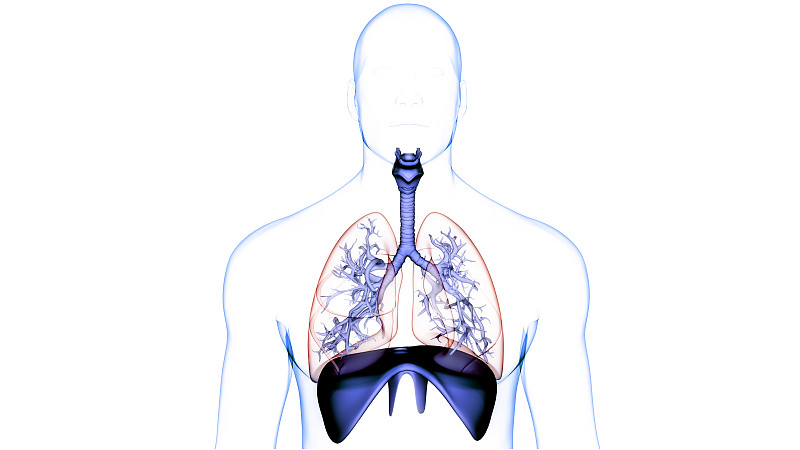

人体呼吸系统肺解剖学详情

JPG